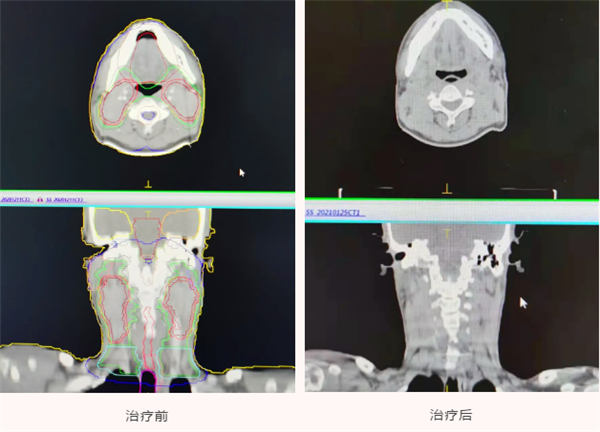

放疗科主任夏火生与其团队根据李先生的病灶大小和位置一起为李先生量身定制出最佳的放射治疗方案。放疗医师用CT等影像学设备重建肿瘤三维结构,建成一个与肿瘤一致的放射线3D立体靶区,射线从不同方向对肿瘤照射,用计算机精确控制放射线的剂量,使得较高剂量的射线精确集中在肿瘤上,用放射线最大程度的杀灭肿瘤细胞,而保护肿瘤周围的正常组织免受过高剂量的辐射,实现精确制导,精确狙击。

经过46天、30多次的放射治疗后,经核磁复查显示,李先生脖子两侧肿块已完全消失,李先生和家人都非常高兴。从入院那一天开始,他就受到放疗科和耳鼻喉科医务人员的悉心照料的精心治疗,也正是因为这两个科的共同努力才使他克服了各种困难,顺利完成了放疗,终于可以出院回家了。

春节将至,1月27日,是李先生和家人返乡的日子,一大早,他们一起来到耳鼻喉科和放疗科向医护人员们表示感谢,并带来锦旗,感谢燕化医院的医护人员对他的治疗及护理。回想起确诊时的恐慌、病情的复杂以及当地医生对治疗的为难,从治疗前双侧颈部肿大淋巴结压迫血管引起的头痛,到放疗后肿瘤的一天天变小,再到现在收获了惊喜的疗效,以及这段时间来所感受到燕化医院的热情细心的服务,千言万语不知从哪说起,只是道不尽的“谢谢!感谢你们!是您挽救了我的生命!”